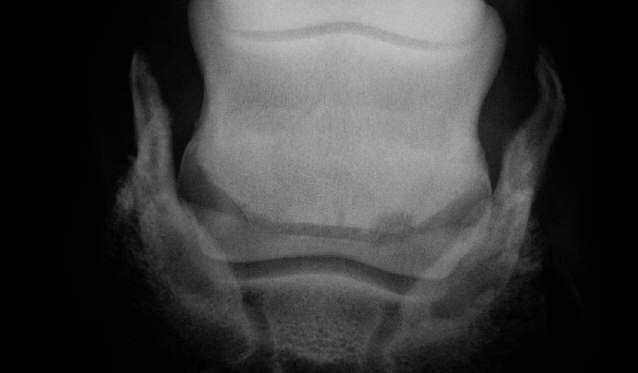

Zubildungen

Starke Zubildung am oberen und unteren Rand. Im osteolytischen Bereich rechts evtl. Ausrissfraktur.